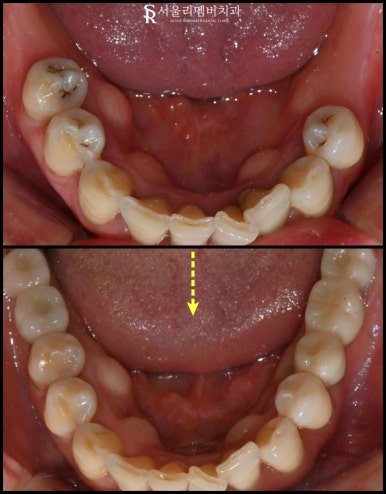

구강 카메라로 찍어 진단 시작하겠습니다.

육안으로 보기에

잇몸 부근이 거뭇거뭇한 게

치태나 치석이 많이 쌓여있고

양쪽 아래쪽 어금니들이 없는 걸

관찰할 수 있습니다.

한쪽을 자세하게 보면

대합치가 빈 곳을 향해 정출된 것을 볼 수 있죠.

착색도 심하여 스케일링 받은 지

오래됐다는 것을 알 수 있었습니다.

관리가 안 된 구강입니다.